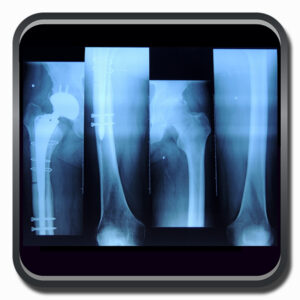

Algumas Cirurgias Complexas realizadas por profissionais da COFIB: